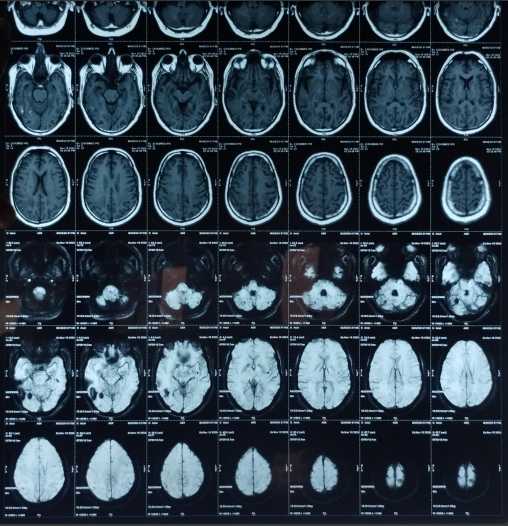

The patient’s routine blood investigations were normal. Serology for HIV, hepatitis B, C, and syphilis was negative. His MRI brain showed a parenchymal bleed in right temporo occipital regions with intra-ventricular leakage of blood and tiny petechial haemorrhage in brain parenchyma bilateral. extensive signal changes in cerebellar hemisphere, bilateral gangliothalamocapsular region, pons, midbrain and deep white matter of both cerebral hemisphere? Microangiopathy? CADASIL.

Early-onset dementia (onset before age 65) is a thought-provoking ailment with many possible causes, including early-onset familial Alzheimer’s disease, frontotemporal lobar degeneration, Parkinson’s dementia, Lewy body dementia, disorders of amino acid and organic acid metabolism, leukodystrophies, lysosomal storage diseases, disorders of metal metabolism, and mitochondrial diseases [6]. In our patient, the history, physical examination, laboratory investigations, and neuroimaging were not suggestive of these causes and prompted the search for a rare etiology. The most common MRI finding associated with CADASIL is basal ganglia and white matter hyperintensities in T2-weighted sequences that start as punctate or nodular foci and then often become confluent, extensive, and usually symmetrical, mainly in the periventricular region, anterior temporal pole, external capsule, the centrum semiovale, and frontal and parietal areas. In our patient, diagnosis was made mainly from MRI findings as seen in fig. 1, 2.

Fig. 1: Tiny petechial hemorrhages are seen in bilateral basal ganglia, white matter of both cerebral hemisphere, midbrain, pns and cerebellum. Diffuse cerebral and cerebellar atrophy is seen with enlarged ventricle due to atrophy. Acute to subacute parenchymal bleed is seen in righttemporo–occipital region. minimal intraventricular leakage of blood is also seen in 4th ventricle